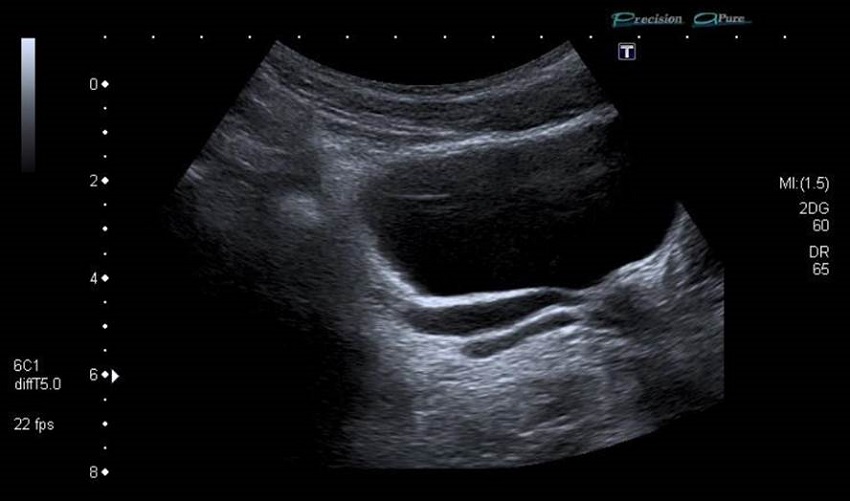

Se realiza la ecografía abdominal, donde se objetiva un riñón único derecho, no claramente compensador (figura 1). No se identifica el riñón izquierdo, pero se visualizan dos imágenes quísticas retrovesicales izquierdas, alargadas, que parecen desembocar en la próstata o el cuello vesical (figura 2). La más posterior, de 0,4 x 2,3 cm, probablemente corresponda a una dilatación de la vesícula seminal o del quiste mesonéfrico; el anterior, de 0,6 x 4,2 cm, podría corresponder a una dilatación del divertículo del remanente ureteral ciego con desembocadura baja (figura 3).